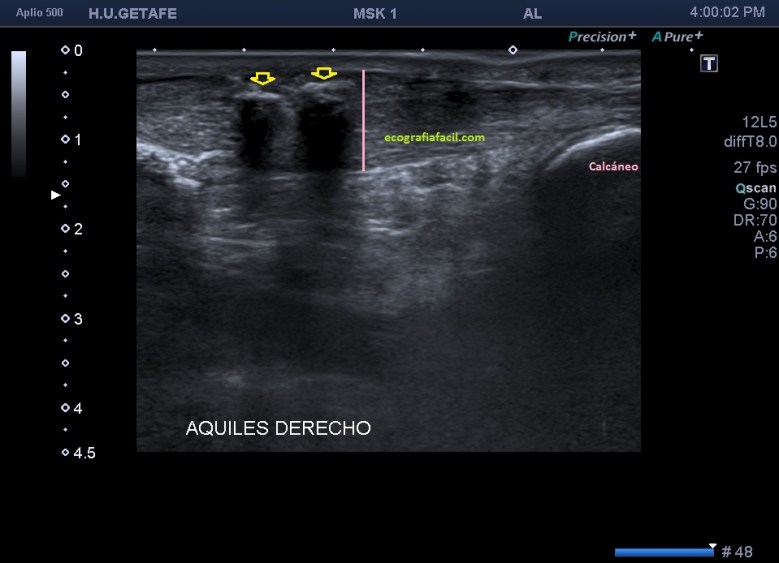

Si observamos la bursitis retroaquílea de la imagen 11(flechas amarillas), además la exóstosis de la imagen 13 y deformidad en la piel, observable sin ecografía podemos estar ante un síndrome de Haglund de esos de libro…y tendremos una imagen ecográfica como la de la imagen 14.

Como has visto en la imagen 1, la bursa retroaquílea no debe verse, ese receso debe tener como mucho una mínima cantidad de líquido, que como digo es normal, pero no lo que observamos en la imagen 11 donde vemos una imagen heterogénea ocupando esa región.